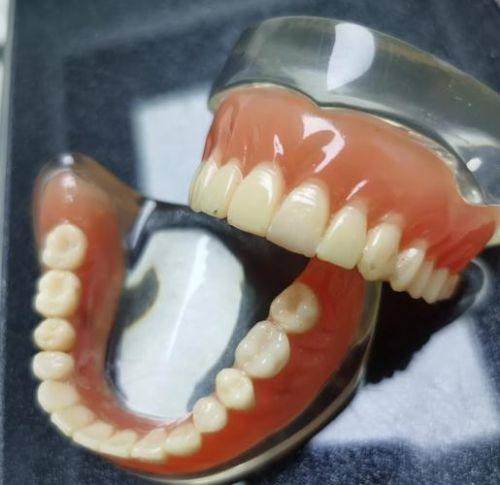

活动义齿一般多少钱一颗费用?2026年最新价格揭秘! 文章揭秘2026年活动义齿最新价格。通常镶活动假牙一颗1000 - 3000元,不同类型费用有别。如隐形义齿1000 - 1200元,便宜但寿命短、咀嚼差;钴铬合金等1500 - 2000元,强度好、使用久;纯钛基托2000 - 3000元,舒适美观。此外,地区、医院等级和医生水平也影响价格,选义齿要综合考量。 活动义齿 2026年03月04日 0 点赞 0 评论 7 浏览

活动义齿哪种最舒服还不伤害基牙?揭秘3种最佳选择! 本文围绕“活动义齿哪种最舒服还不伤害基牙”展开。首先强调了活动义齿舒适与护基牙的重要性,接着介绍了纯钛金属基托活动义齿等三种义齿的特点,包括舒适度、对基牙的影响、价格等。还给出选择建议,要考虑口腔状况、经济因素,并听取医生建议。最后提醒佩戴后注意适应期、清洁和饮食,综合考量选适合自己的义齿。 活动义齿 2026年03月04日 0 点赞 0 评论 12 浏览

补一颗活动义齿多少钱?揭秘真实费用与选择技巧! 本文围绕补一颗活动义齿的费用及选择技巧展开。费用大致在100 - 300元,受材料、修复难易、医院级别、当地经济等因素影响。不同材料义齿各有特点和价格区间。选择时要综合自身情况,选正规机构,多对比。此外,后期维护有成本,需正确佩戴清洁。提醒大家综合考量价格、质量和舒适度,必要时咨询医生。 活动义齿 2026年03月04日 0 点赞 0 评论 7 浏览